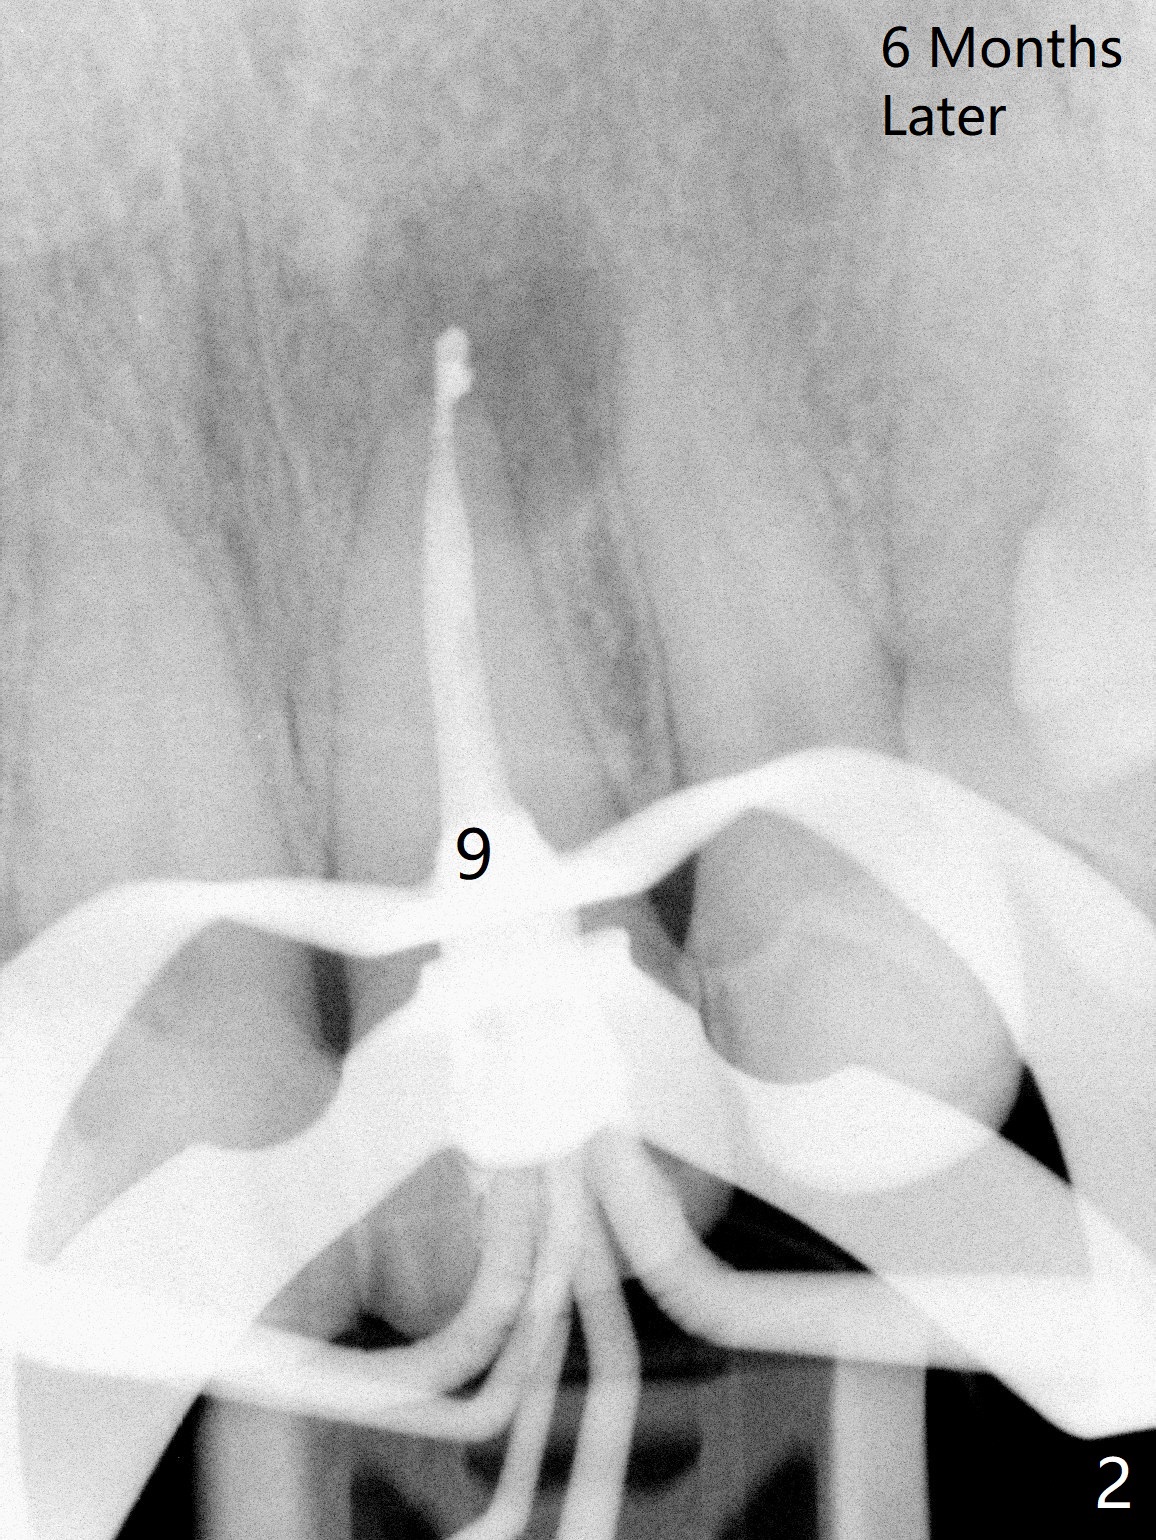

A 47-year-old woman (dental phobic) presented to clinic 9.5 years ago with periapical radiolucency (PARL) at #7 and 9 (Fig.1). RCT was done at #9 because of fistula and symptom 6 months later (Fig.2). While PARL increases at #7 without symptom, that at #9 disappears 8.5 years postop. Three months later, the patient returns for #7 RCT because of the abscesses (Fig.4 *) and pain. Intraop PA is taken with a 30/.06 rotary file in the canal with 19 mm working length (Fig.5). After use of #15 hand file for 20 mm, Ca(OH)2 paste is applied in the canal. When the rubber dam is removed, the abscesses enlarge (Fig.6), which may be related to sodium hypochlorite leakage. A dental explorer is used to try to find a bony opening to the large PARL without success (Fig.7). A postop PA reveals the leakage of Ca(OH)2 paste (Fig.8). Review of the preop PA (Fig.3,9) and intraop PAs (Fig.5,10) shows possible apical resorption and open apical foramen, which is the basis for the paste leakage (Fig.8,11). Careful analysis (with magnification and room light off) of pre- and intra-op PAs should be able to avoid use of #15 hand file out of apical constriction and the complication. The abscess has receded 1 month later (Fig.12). The paste has been resorbed 1 month later (Fig.13). A 30/.06 Gutta Percha is inserted at 18.5 mm (Fig.14 vs. 30/.06 file at 19 mm, 15 file at 20 mm last visit). Fig.15 is the final PA after closure of the access with composite (Fig.15).